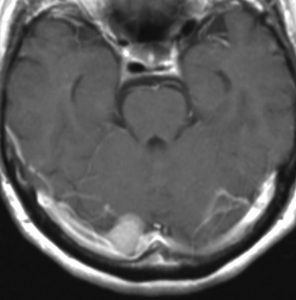

- 下のMRIは66歳の女性に脳ドックで偶然見つかった髄膜腫です.左の写真は1995年,右は2005年です。10年間で全く大きくなっていません